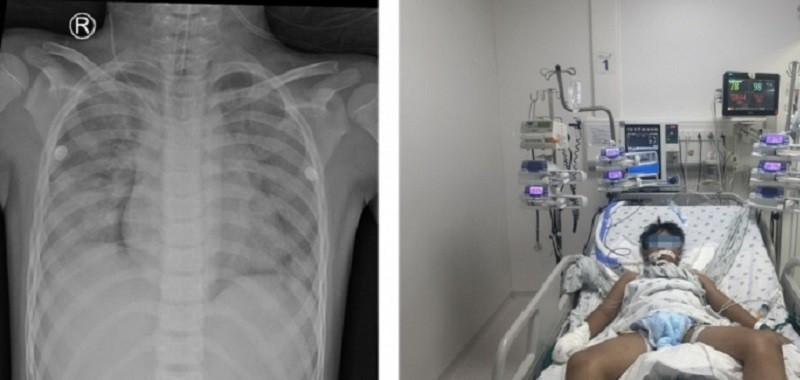

Thời điểm nhập viện, bệnh nhi bị tổn thương cả hai bên phổi mức độ rất nặng (ảnh: BSCC)

Theo BS Nguyễn Minh Tiến, khi tiếp nhận, bệnh nhi trong tình trạng hôn mê, tím tái, độ bão hòa oxy trong máu ngoại vi SpO₂ chỉ còn 78% (bình thường trên 95%), xuất hiện các cơn co gồng toàn thân. Kết quả X-quang phổi ghi nhận tổn thương lan tỏa cả hai bên phổi; CT-Scan não – ngực – bụng cho thấy bệnh nhân bị phù não, đông đặc và thâm nhiễm hai phổi nhưng may mắn là không ghi nhận tổn thương các tạng trong ổ bụng.

Xét nghiệm khí máu động mạch cho kết quả toan chuyển hóa và thiếu oxy máu nặng, lactate máu tăng cao, phản ánh tình trạng thiếu oxy mô kéo dài. Bệnh nhi được chẩn đoán ngạt nước, phù phổi cấp, thiếu oxy não và viêm phổi hít.